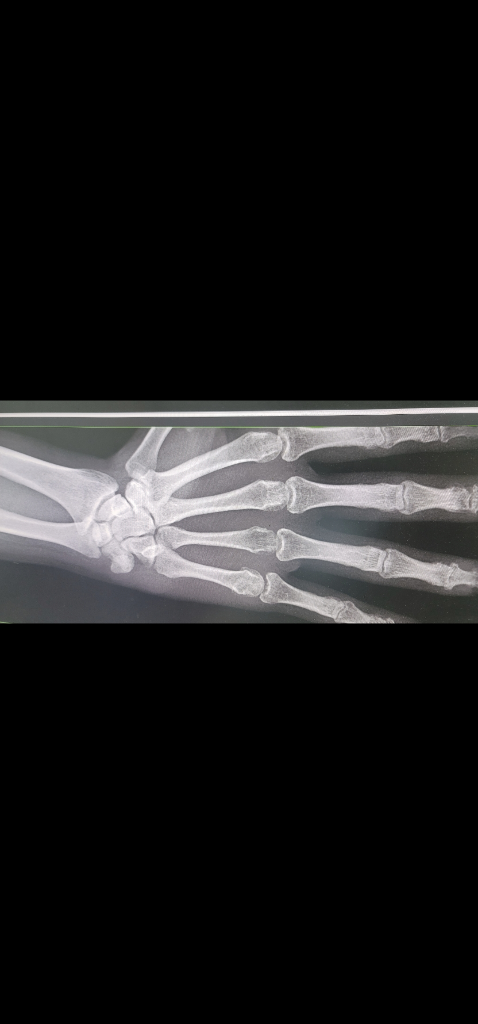

오른손 네번째 손가락 중수골 골절로 핀 고정술로 치료받고 8주차 입니다. 핀은 2주 전에 제거하고 재활하고 있습니다. 수술한 병원이 거리가 있어서 근처 병원에서 엑스레이 촬영 후 진료 봤습니다.

1. 네번째 중수골 수술한 부위 뼈가 붙었는가?

2. 손목뼈(네번째, 다섯번째 중수골 끝 부분)에 긴 타원형으로 보이는 흰색점은 이상 없는가?

입니다. 의사 분이 그 부위를 만져봤을 때 통증이나 특이점은 없었습니다.

사진이 너무 작아서 보이지 않습니다.

더 확대해서 올려주시면 이후에 다시 확인하다록 하겠습니다